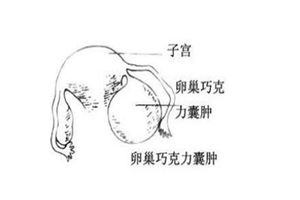

巧克力囊肿是子宫内膜异位症的一种常见类型,子宫腔的异位内膜在卵巢中生长,形成囊肿,因为囊液呈巧克力颜色而得名。

因为是子宫内膜,即使不在子宫腔,它也会受到月经周期雌孕激素波动的影响,来一次月经,就长一点。然后脱落的内膜又不能像月经一样排出,只能呆在囊肿里,越积越多。囊肿越来越大。

5.囊肿破裂

巧克力囊肿长大到一定程度,有可能会发现破裂,出现一侧下腹疼痛,或轻或重,严重者需急诊手术。